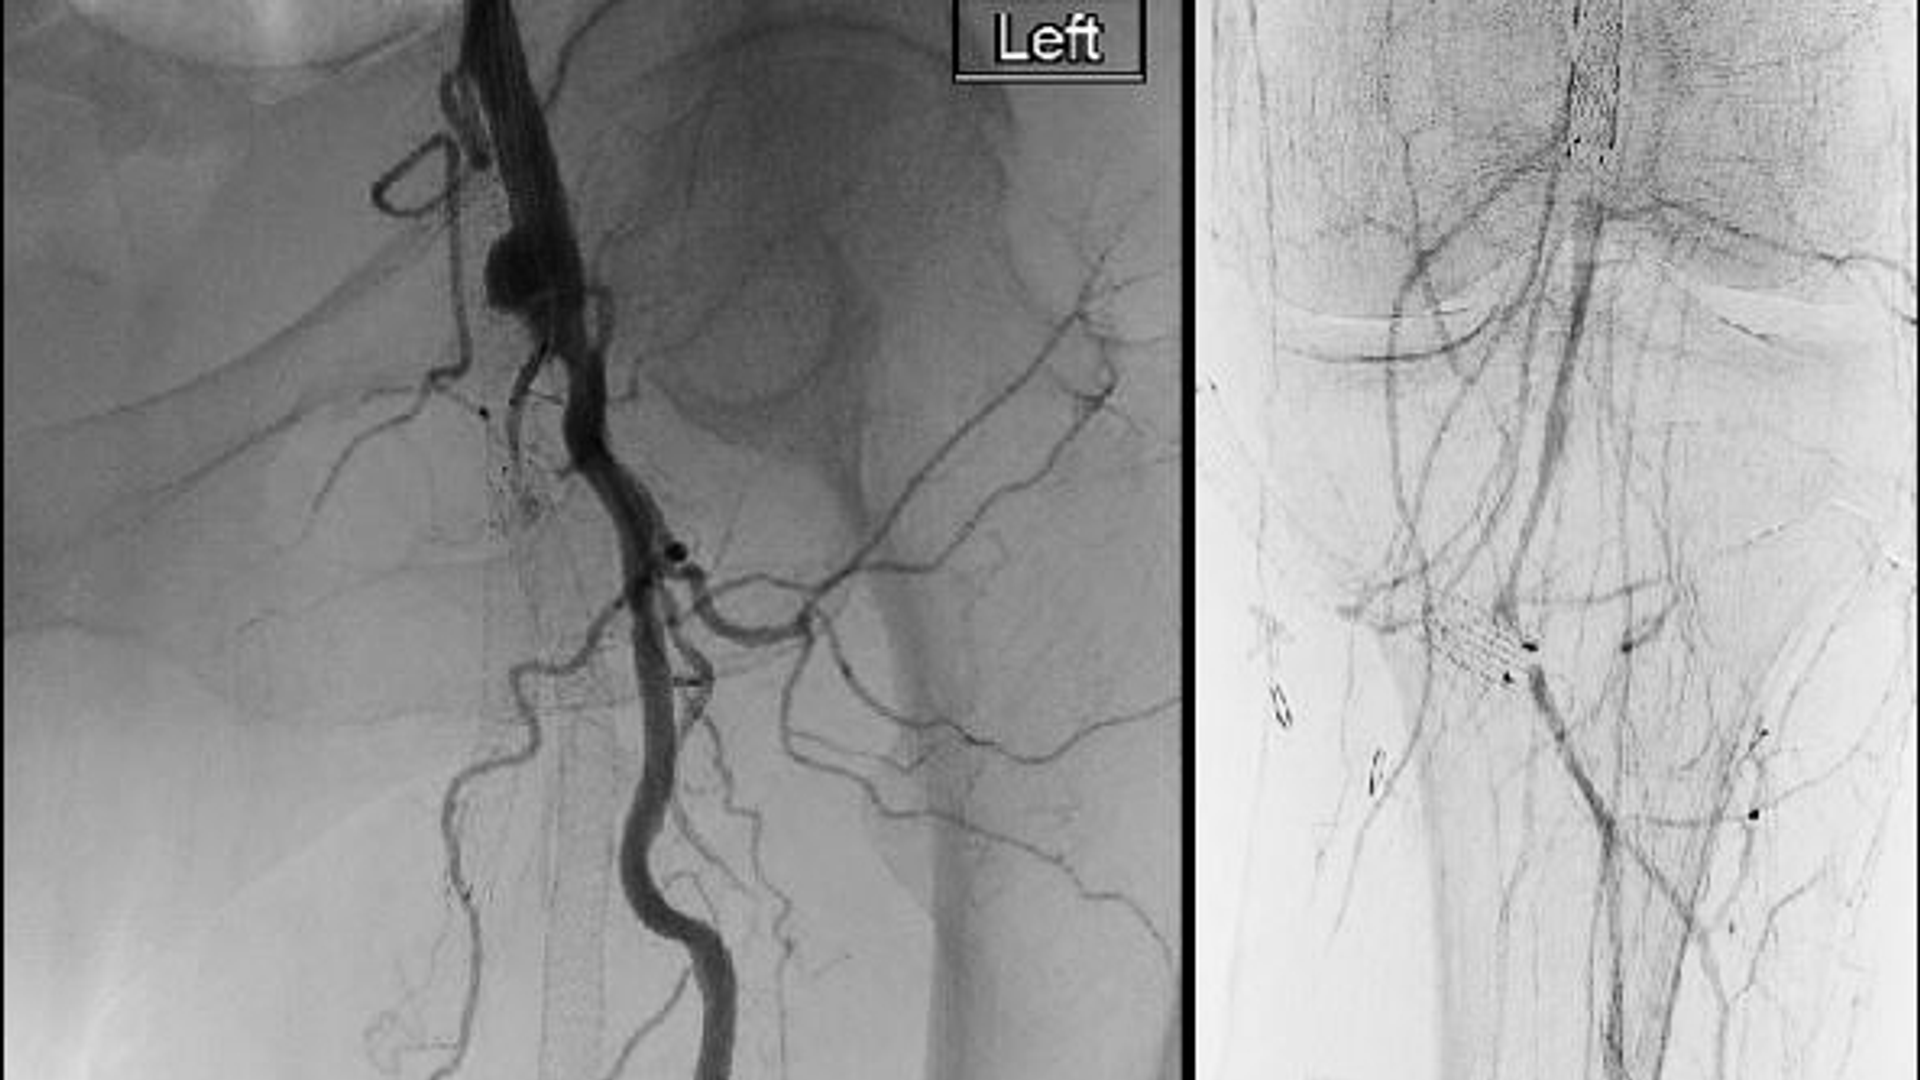

Four scans demonstrate the restoration of blood flow to the lower leg when blood is diverted from the femoral artery into stents in the femoral vein to bypass a long clot

Figure 2 - Detour completion angiogram shows widely patent transmural arterial bypass with inline flow to the popliteal artery and tibial runoff retained and brisk as compared to prior.